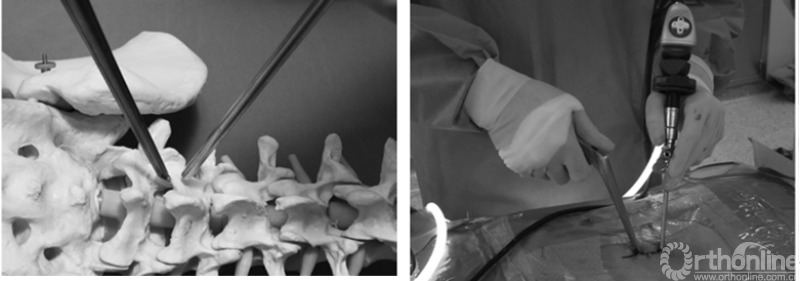

PE-TLIF为经椎间孔入路,使用上关节突导向切除装置定向磨除上关节突,扩大椎间孔区域,在10mm脊柱内窥镜辅助下进行腰椎的减压、椎间植骨及融合器植入,最后辅以经皮置入椎弓根螺钉。

随着计算机导航技术在脊柱外科领域的应用越来越广,2018年周跃教授团队率先报道了计算机导航系统辅助下的经皮腰椎减压融合技术。

针对以上问题,海涌教授和杨晋才教授团队自主创新设计了经皮内镜辅助下经椎间孔腰椎减压融合术(Percutaneous Endoscopic Transforaminal Lumbar Interbody Fusion, PE-TLIF)以及配套的手术相关器械,初步临床结果令人满意,无神经损伤和融合器移位等并发症发生。